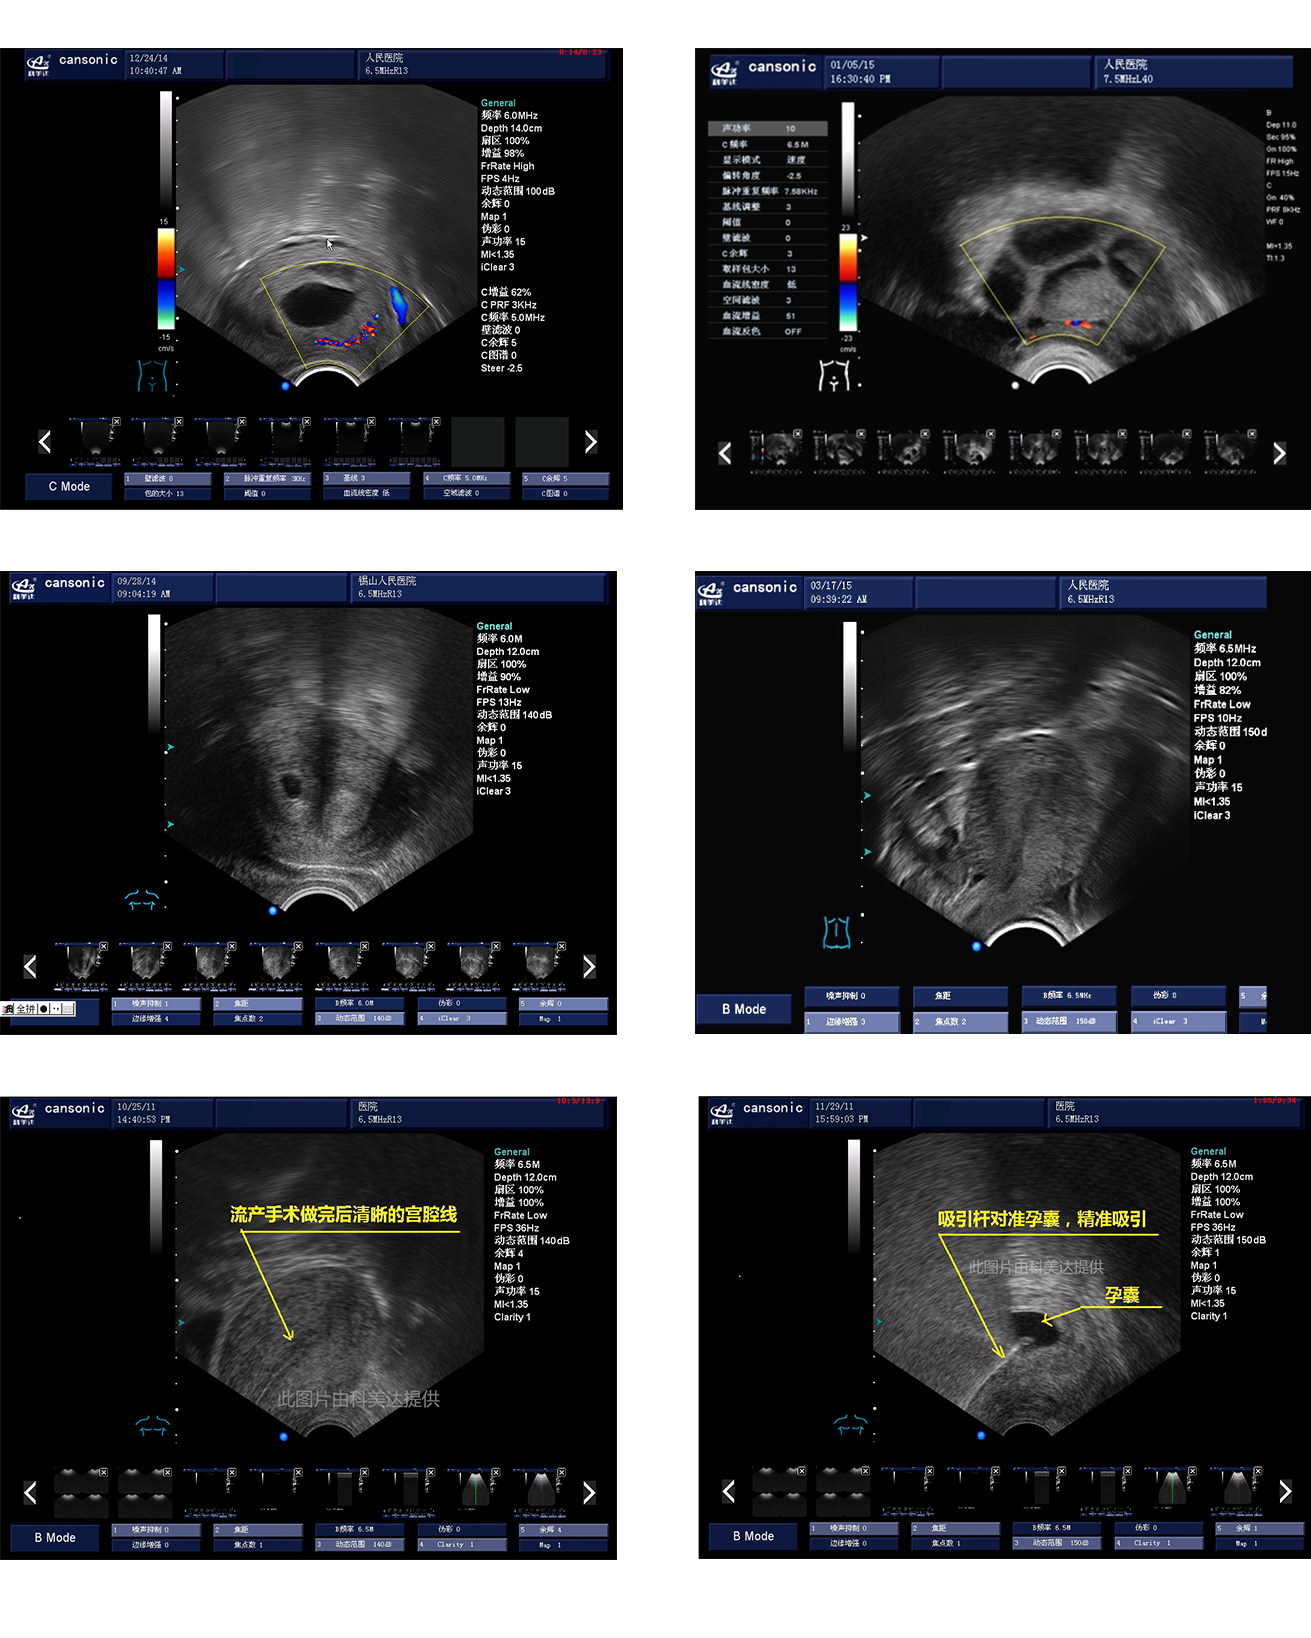

临床图示